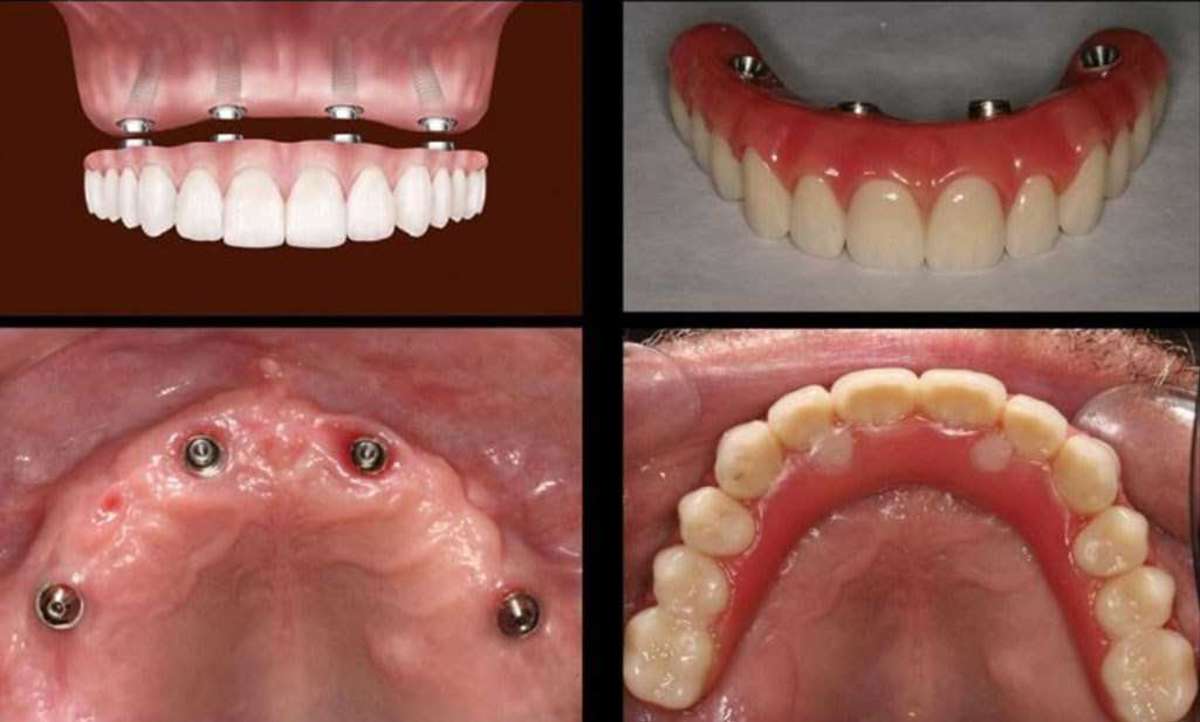

Dental implants are a popular choice for tooth replacement. If you are considering Dental Implants in Houston Midtown, VIP Dental Implants is the perfect place for you. We offer a variety of dental implant options, so you can choose the one that is right for you. Contact us today to schedule a consultation and learn more about dental implants.